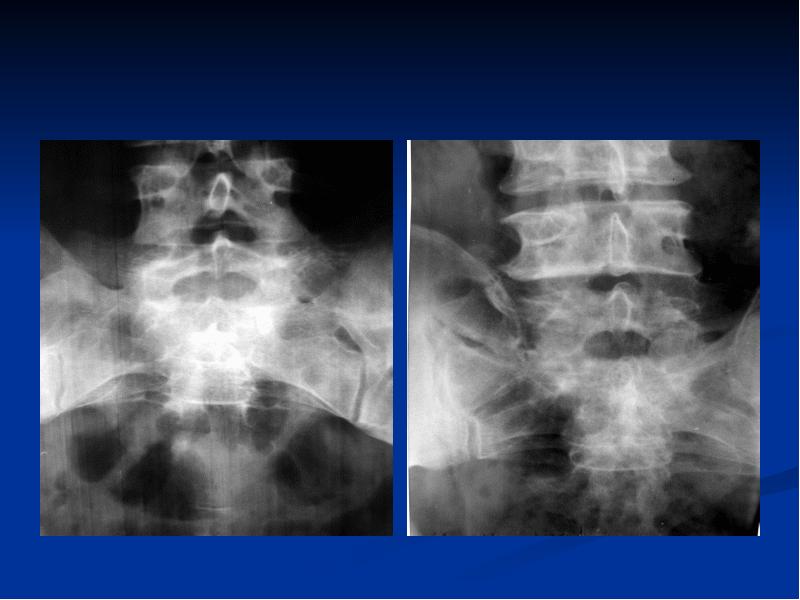

Фильтры в рентгенологии: как улучшить качество изображений